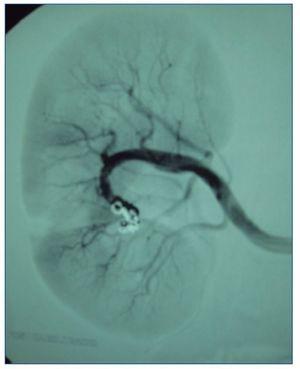

Figura 2. Desaparición de la fístula arteriovenosa asociada tras embolización con microcoils.

Se trata de una mujer de 59 años, con antecedentes de hipercolesterolemia y artrosis, que se remite a las consultas de nefrología para estudio de microhematuria persistente y asintomática, sin proteinuria, y función renal normal. Se realiza ecografía renal que muestra riñones de medida y morfología normales. En el seno del riñón derecho se aprecia una imagen hipoecogénica de 17 mm, que en el estudio Doppler se llena completamente de flujo sanguíneo, lo que sugiere la presencia de una MAV. Posteriormente, se realiza una angio-TC, que muestra ambas arterias de morfología y calibre conservados. Destaca la presencia de una lesión hipercaptante de 17 × 22 mm de diámetro en el seno del riñón derecho, con llegada de vasos arteriales y opacificación precoz de la vena renal, lo que indica la existencia de shunt arteriovenoso. Se practica arteriografía no selectiva y selectiva renal derecha por abordaje femoral. Se identifica una imagen seudoaneurismática de 2 cm localizada intrarrenalmente en el polo inferior, con importante FAV asociada (fig. 1). Se procede a estudio supraselectivo intrarrenal, que identifica el pedículo aferente único. Se emboliza selectivamente con microcoils de 4/4 y 3/3 mm, con excelente resultado morfológico final: oclusión del seudoaneurisma, desaparición de la FAV asociada y preservación de la práctica totalidad del parénquima (fig. 2). Tras más de 5 años de dicho procedimiento angiorradiológico, la paciente permanece asintomática y con controles ecográficos sin evidencia de nuevas alteraciones morfológicas.